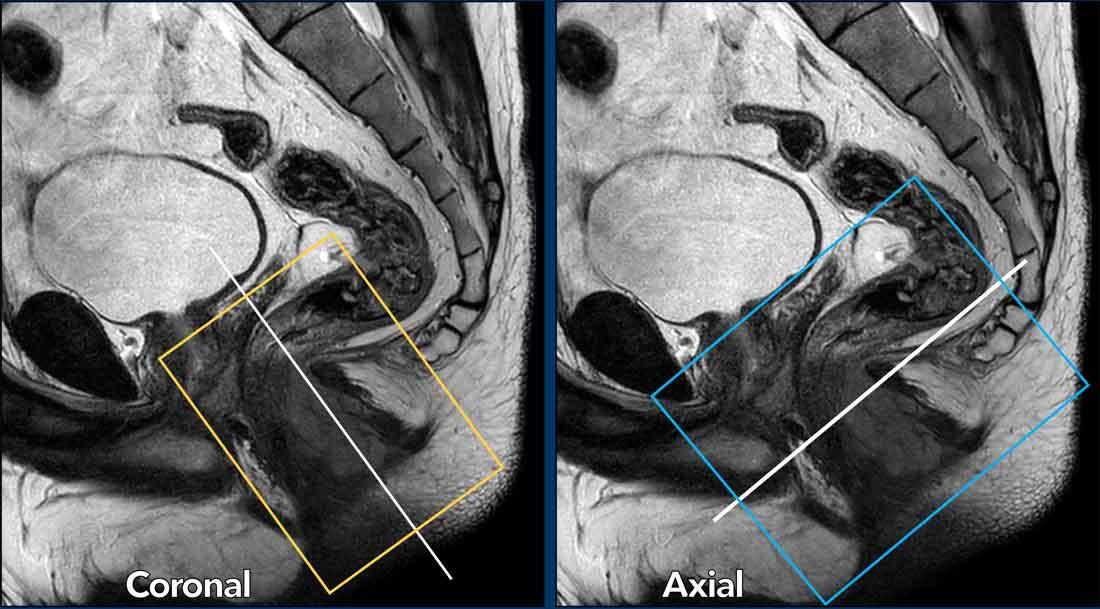

Góc lấy chuỗi xung

Chuỗi xung T2W độ phân giải cao mặt phẳng coronal được lập kế hoạch song song với ống hậu môn nhằm tối ưu hóa khả năng hiển thị các lớp khác nhau của ống hậu môn.

Chuỗi xung mặt phẳng ngang (transverse) được lập kế hoạch vuông góc với ống hậu môn.